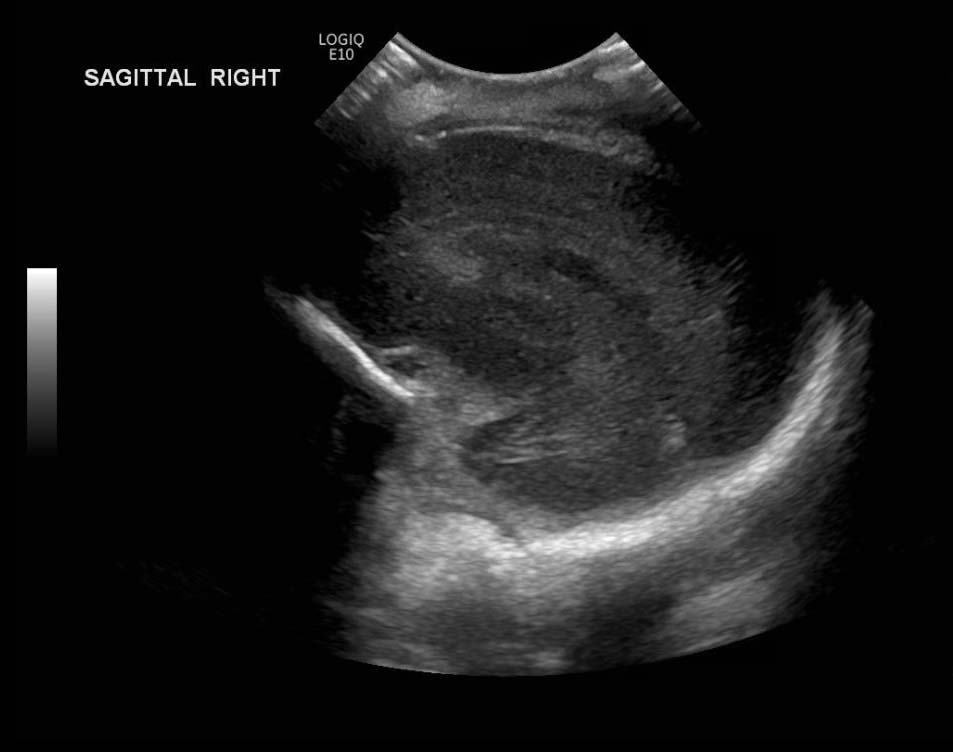

Age: 4 days (born at 24 weeks)

Sex: Male

Indication: Evaluate for germinal matrix hemorrhage

Grade 2 germinal matrix hemorrhage

Sample ReportLeft germinal matrix hemorrhage involving the caudothalamic groove and layering in the occipital horn of the left lateral ventricle without hydrocephalus (grade 2).

No abnormal brain parenchymal echogenicity or extra-axial collections.

Premature sulcation pattern.